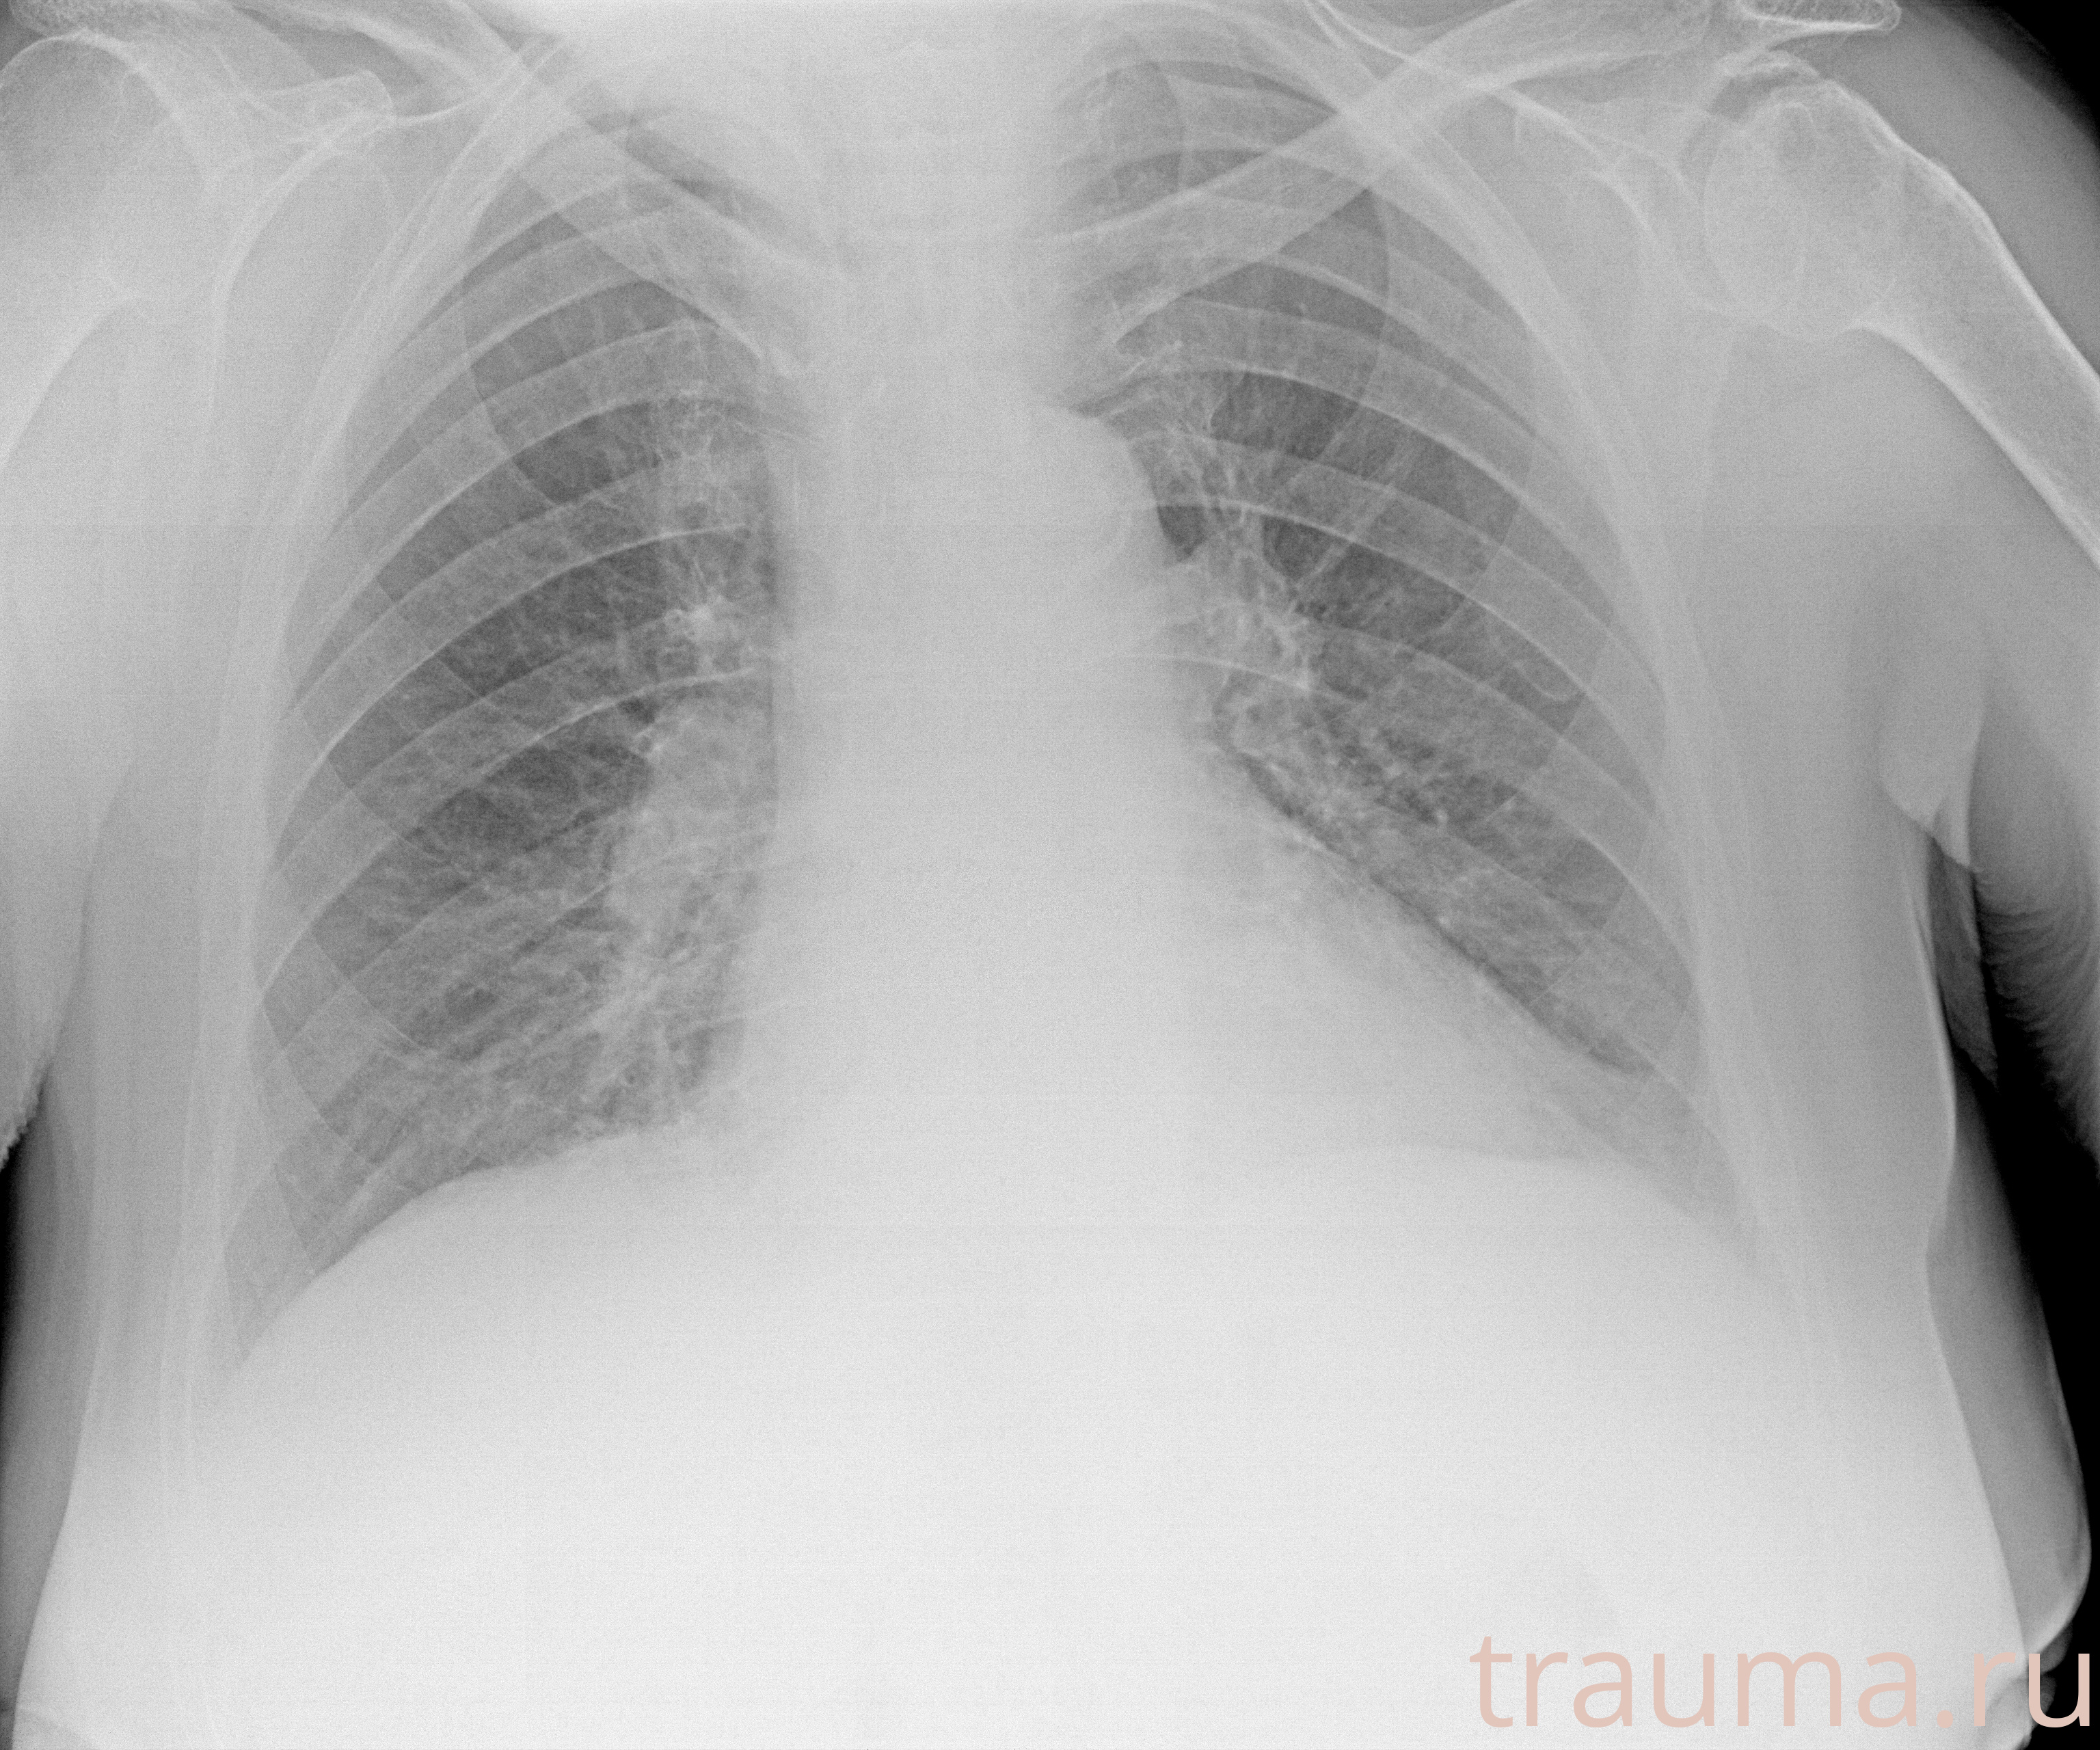

Рентген на дому: по вашему адресу приезжает врач-рентгенолог, травматолог-ортопед с мобильным рентгеновским аппаратом, проводит диагностику травмы или заболевания, делает необходимые рентгенограммы, дает рекомендации по дальнейшему лечению. Получить качественные снимки в домашних условиях возможно благодаря уникальной методике, разработанной МосРентген Центром для института  Склифосовского

при переломе шейки бедра и пневмонии от компании МосРентген Центр - партнера Института имени Склифосовского